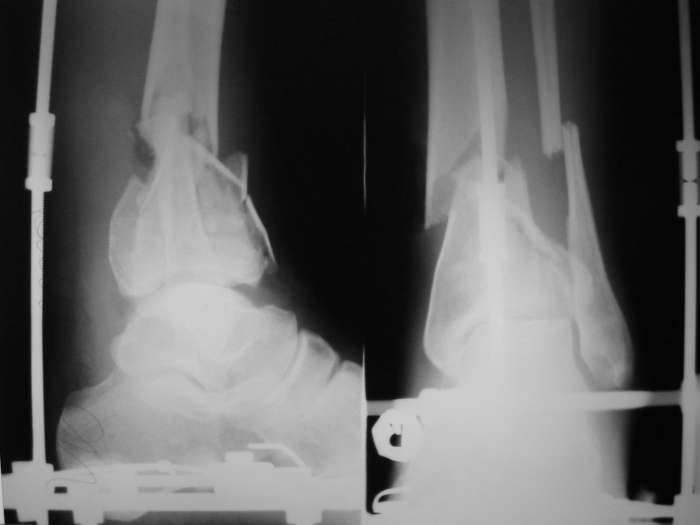

В понедельник в операционной выполнена санация раны с резекцией всех участков кости выступающих в просвет раны, удалены свободнолежащие фрагменты, некрэктомия. Промыто и заполнено салфеткой с некролитической мазью. Дополнительно проведена спица в с/3 голени. "Вытянул" голень до анатомичекой длины. После операции получил неприятный "сюрприз" - дистальный фрагмент б/б кости "разнесло". Снимки выложу завтра. Думаю опять ослабить дистракцию с целью собрать "в кучку" отломки дистального фрагмента, а также для

уменьшения раневой полости (которая меня, по-правде говоря, ужасает).

Состояние раны: постепенно очищается, заполняется грануляциями с участками фибрина. Воспаление мягких тканей вокруг раны купировано. В глубине раны, ближе к дистальному отломку, остается небольшой "гнилой угол" с весьма скудным отделяемым. Две "большие" перевязки в течение недели, с частичными некр- и секвестрэктомиями в условиях операционной.

При закрытой попытке поймать и собрать отломки дистального фрагмента спицами с напайками, удача покинула меня.:-(